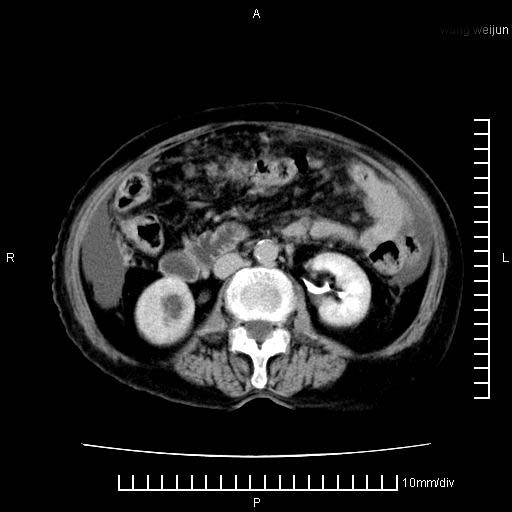

标题: CT28280:腹部增强:女性,80岁

上腹疼痛月余,外院核磁诊断胰腺癌。现临床示右下腹可明显触及包块,可片子上怎么没有看到?

胰腺结构模糊,胰尾部见囊性包块,周围脂肪密度增高,左肾前筋膜增厚,胸水、腹水。不符合胰腺ca伴腹膜腔转移。考虑胰腺炎伴假性囊肿形成、胸腹腔积液。

右肾盂囊肿。

1)考虑胰腺癌并胰腺假性囊肿形成。2)肝内低密度灶,不排除转移。3)右肾盂积水。4)腹水。5)右侧胸腔积液并右肺下叶部分膨胀不全。